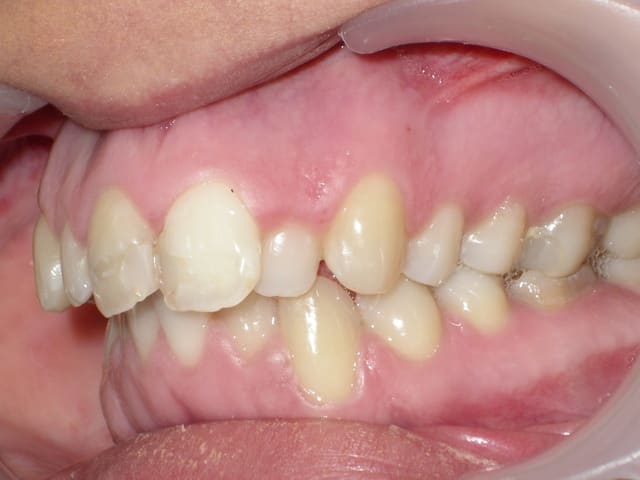

j'aurais voulu avoir vos avis concernant ce cas: il s'agit d'une femme de 23 ans qui desire ameliorer son profil et son esthetique buccal

elle presente une full classe II subdivision droite associé a la perte de la 46, une deviation importante des milieux inf vers la droite, une retrogenie associée à un contexte hyperdivergent.

On est coincé ici par la perte de 46 avec déviation des inférieures à droite et la pseudo classe I dentaire à gauche dans ce profil rétrognathe.

Avulsion 36 pour pouvoir dans un premier temps reculer le secteur inférieur gauche à l’identique du coté droit et récupérer les milieux en créant une classe II dentaire globale, puis avancée mandibulaire chirurgicale de type Obwegeser avec génioplastie.

merci Dancha, j'avais en effet opté pour le meme plan de traitement que toi a savoir:

-Avulsion 36

-correction des milieux

-création d' une classe II dentaire bilaterale et donc d'un surplomb antérieur suffisant pour permettre une chir d'avancée mandibulaire

-et enfin génioplastie.